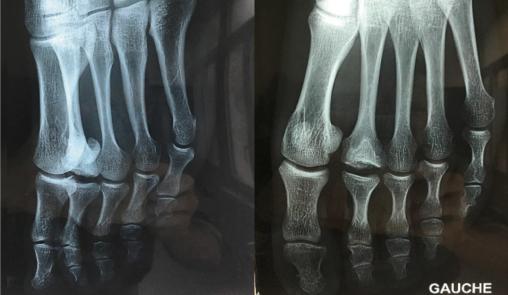

Les radiographies du pied de profil et de face (fig. 2) retrouvent une ostéocondensation, témoignant d’une hyperosotose au niveau de la tête du deuxième métatarsien, probablement séquellaire d’une ancienne fracture selon le compte-rendu radiologique. Le patient, sportif, assure n’avoir jamais eu de fracture.

Le diagnostic est radiologique : ostéocondensation à la phase initiale, trait de fracture plus ou moins visible, élargissement de l’interligne articulaire et aplatissement de la tête métatarsienne si la nécrose est avancée.3 Le risque évolutif est une arthrose métatarsophalangienne.4